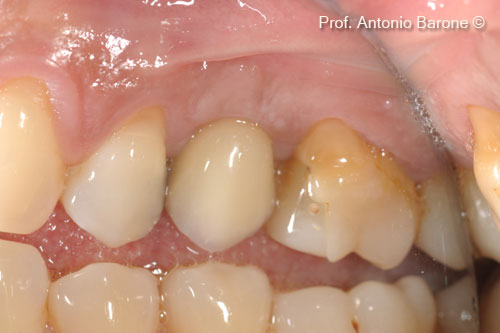

Hình ảnh nhìn từ phía má 3 năm sau khi cấy ghép implant

Hình ảnh lâm sàng mặt ngoài má 5 năm sau khi cấy ghép implant

Hình ảnh lâm sàng mặt ngoài má 7 năm sau khi cấy ghép implant